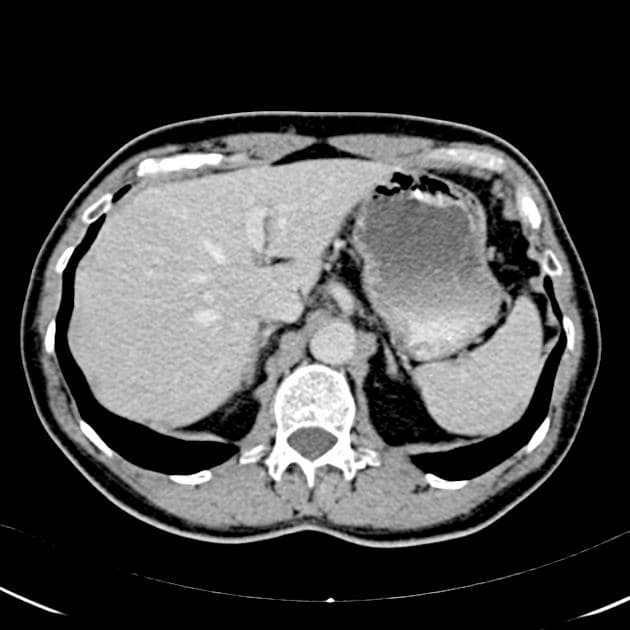

Insulinoma

Các cơn co giật liên quan đến hạ đường huyết nặng.

- Trên hình ảnh trục T2 trọng T2, thấy một tổn thương dạng đặc, hình tròn ở mỏm móc của tụy, có tín hiệu tăng, ranh giới rõ.

- Trên hình ảnh trục T1 trọng T1, thấy tổn thương dạng đặc ở mỏm móc tụy với tín hiệu giảm.

- Trên hình ảnh ADC trục, tổn thương biểu hiện hạn chế khuếch tán (restricted diffusion).

- Trên hình ảnh T1 có tiêm thuốc tương phản gadolinium trục, tổn thương cho thấy tăng quang mạnh (vivid enhancement).

Insulinoma – u tuyến nội tiết tụy tiết insulin, thường lành tính, phù hợp với adenoma (adenoma) của tế bào β đảo tụy, lâm sàng biểu hiện bằng hạ đường huyết do tăng tiết insulin.

- "Insulinoma là u thần kinh nội tiết tụy chức năng phổ biến nhất, thường biểu hiện bằng các triệu chứng thần kinh do hạ đường huyết lúc đói."

- "Trên MRI, insulinoma thường có ranh giới rõ, tăng tín hiệu trên T2, giảm tín hiệu trên T1 và hạn chế khuếch tán, với tổn thương tăng quang mạnh."

- "Mô hình tăng quang 'rì rầm' — tăng quang mạnh ở thì động mạch và tưới thuốc nhanh thoái lui ở thì muộn — là đặc trưng trên hình ảnh có tiêm thuốc tương phản."